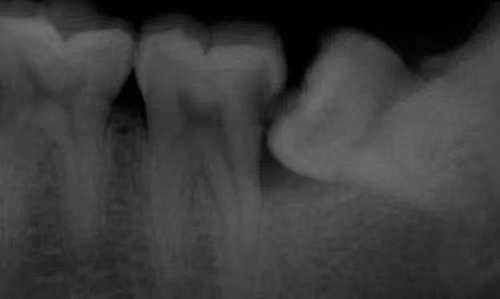

5.邻牙及支持组织的吸收:当阻生的智齿萌出过程中受阻于第二磨牙时,会引发第二磨牙牙根逐渐吸收,严重者可使下颌第二磨牙远中牙根完全吸收,致第二磨牙松动、疼痛。阻生智齿与第二磨牙间常食物嵌塞发生慢性牙周炎,也会造成牙槽骨的炎症性吸收,使第二磨牙反复肿痛。

智齿周围囊性病变:颌骨的牙源性囊性病变好发于未萌出的埋伏牙,而下颌阻生的智齿是主要的好发部位之一。